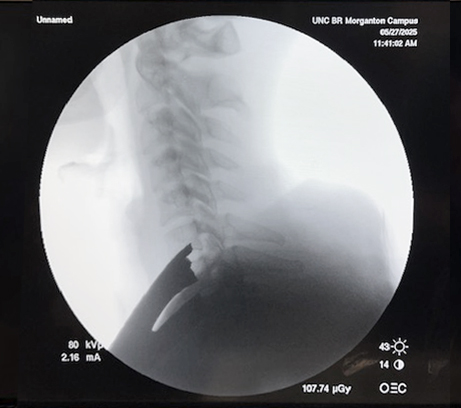

Visualization | Lower Cervical Spine Procedures

Achieve Better Visualization, Especially in Higher BMI patients.